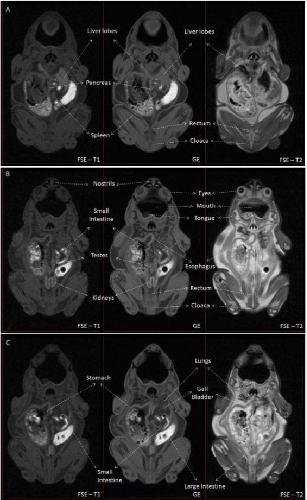

Sex Determination in Two Species of Anuran Amphibians by Magnetic Resonance Imaging and Ultrasound Techniques. , Ruiz-Fernández MJ, Jiménez S, Fernández-Valle E, García-Real MI, Castejón D, Moreno N , Ardiaca M, Montesinos A, Ariza S, González-Soriano J., Animals (Basel). November 18, 2020; 10 (11):